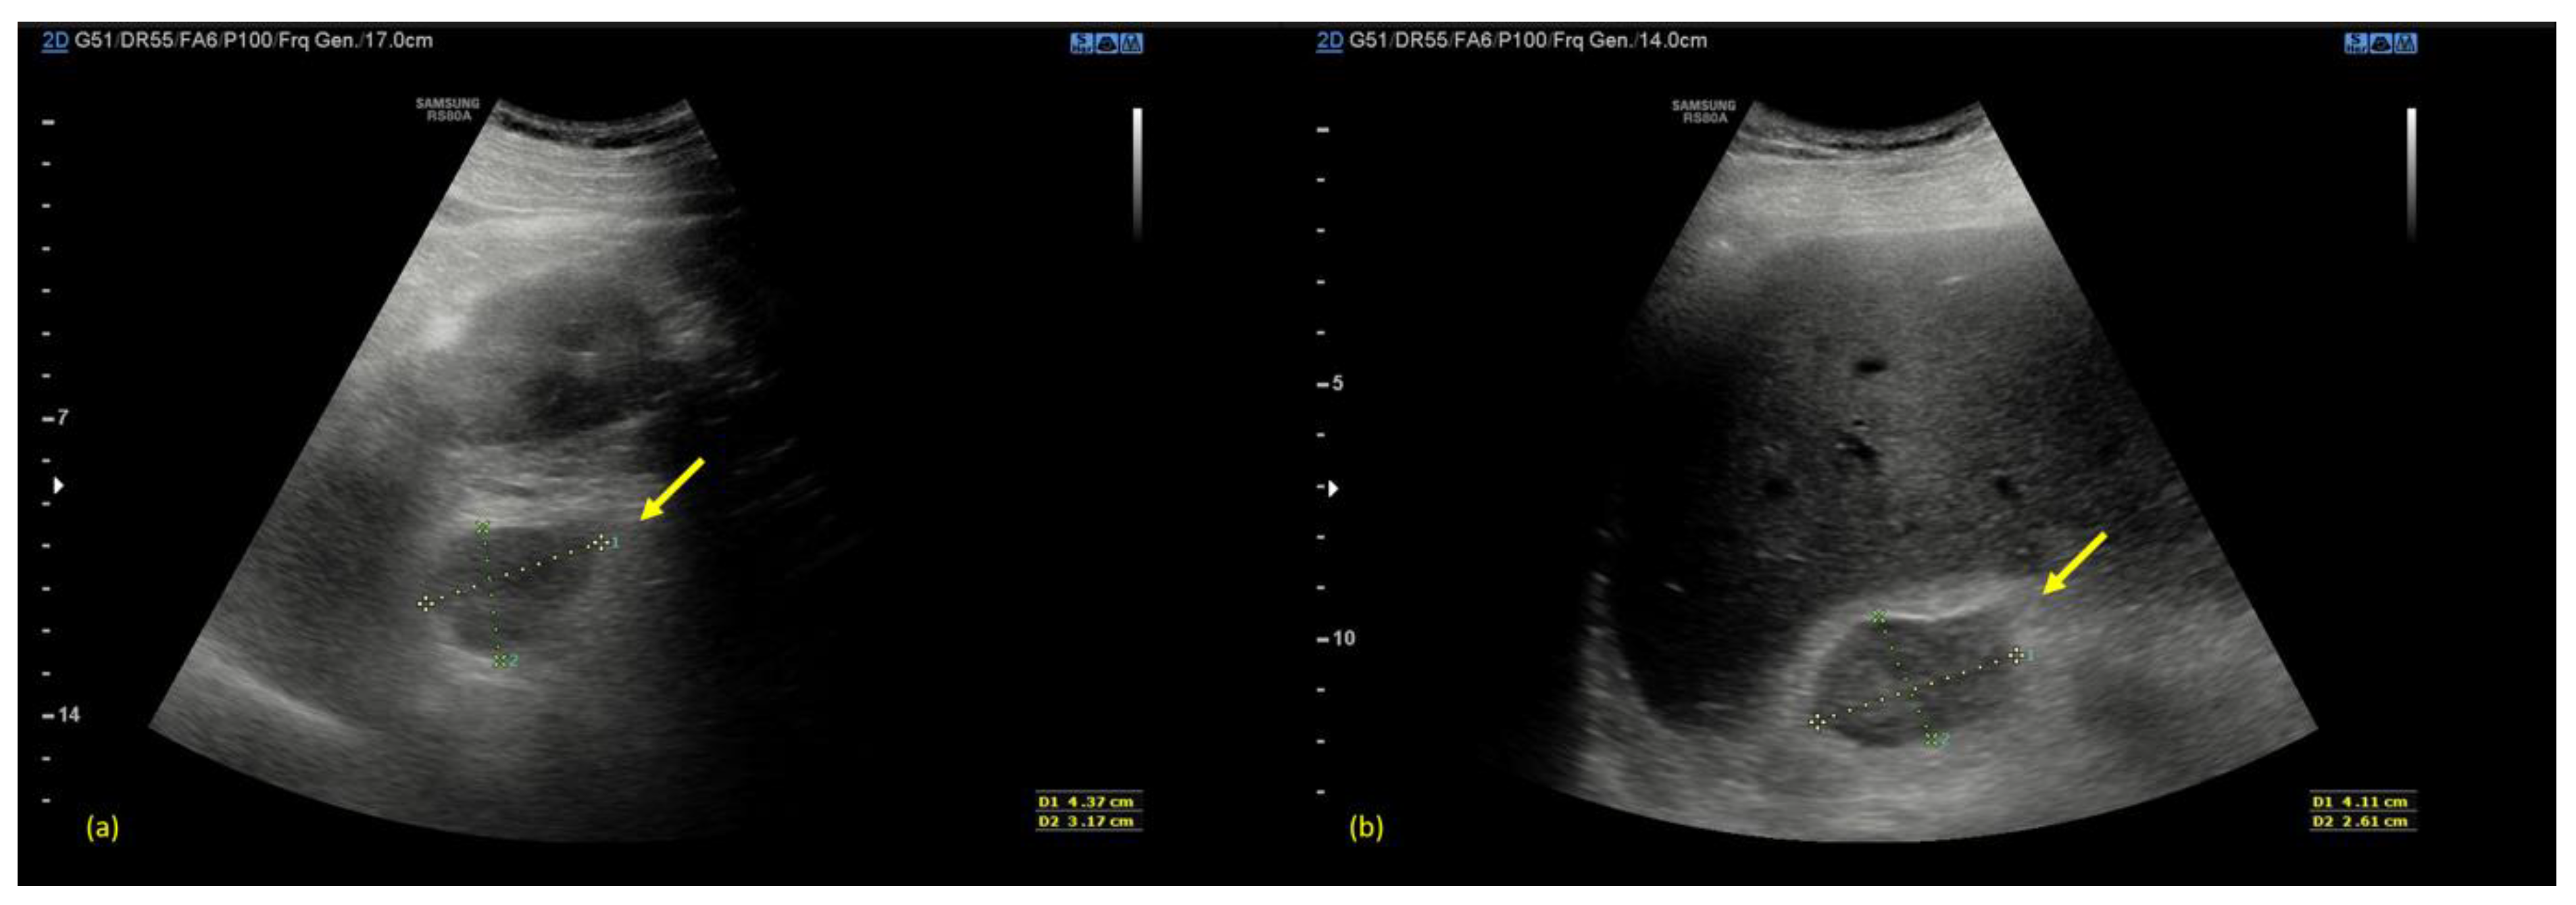

An urgent ultrasonography scan (US) was performed with a convex transducer that revealed an enlargement of both adrenal glands with inhomogeneous echogenicity (Figure 1).

Figure 1.

(a) Arrow indicates the right adrenal gland. (b) Arrow indicates the left adrenal gland. The US Scan shows an enlargement of both adrenal glands with inhomogeneous echogenicity. The right gland measures 41 × 26 mm while the left adrenal gland measures 43 × 30 mm.

If clinically suspected, an urgent CT scan of the abdomen is strongly suggested as the “gold standard” in the diagnosis of adrenal hemorrhage. It usually shows adrenal hematomas that characteristically appear round or oval, often with surrounding strandings of the periadrenal fat. In rare cases, if arterial active bleeding is occurring, a post-contrast blush might be also detected [15,16]. A condition named “adrenal congestion”, which consists in thickening of adrenal glands and the stranding of the periadrenal fat, can be occasionally detected before the hemorrhage [17]. When clinical and laboratory findings are non-specific, as they were in our case, the CT scan may be preceded by a US scan, which can show an increased volume of both the adrenal glands with diffuse or inhomogeneous echogenicity due to the presence of hematomas [18].

In the management of a patient presenting abdominal pain, ultrasonography (US) is usually the first modality to be performed. The pattern of echogenicity of an adrenal hematoma depends on the time since the onset.

During the first days, a hematoma has the look of a mass with inhomogeneous echogenicity. As days go by, the hematoma tends to liquefy, starting to show peripheral heterogeneous echogenicity with a hypoechoic core. Eventually, it tends to become anechoic and appears similar to a pseudocyst. Color Doppler US can be helpful for confirming the absence of vascular signals [20].